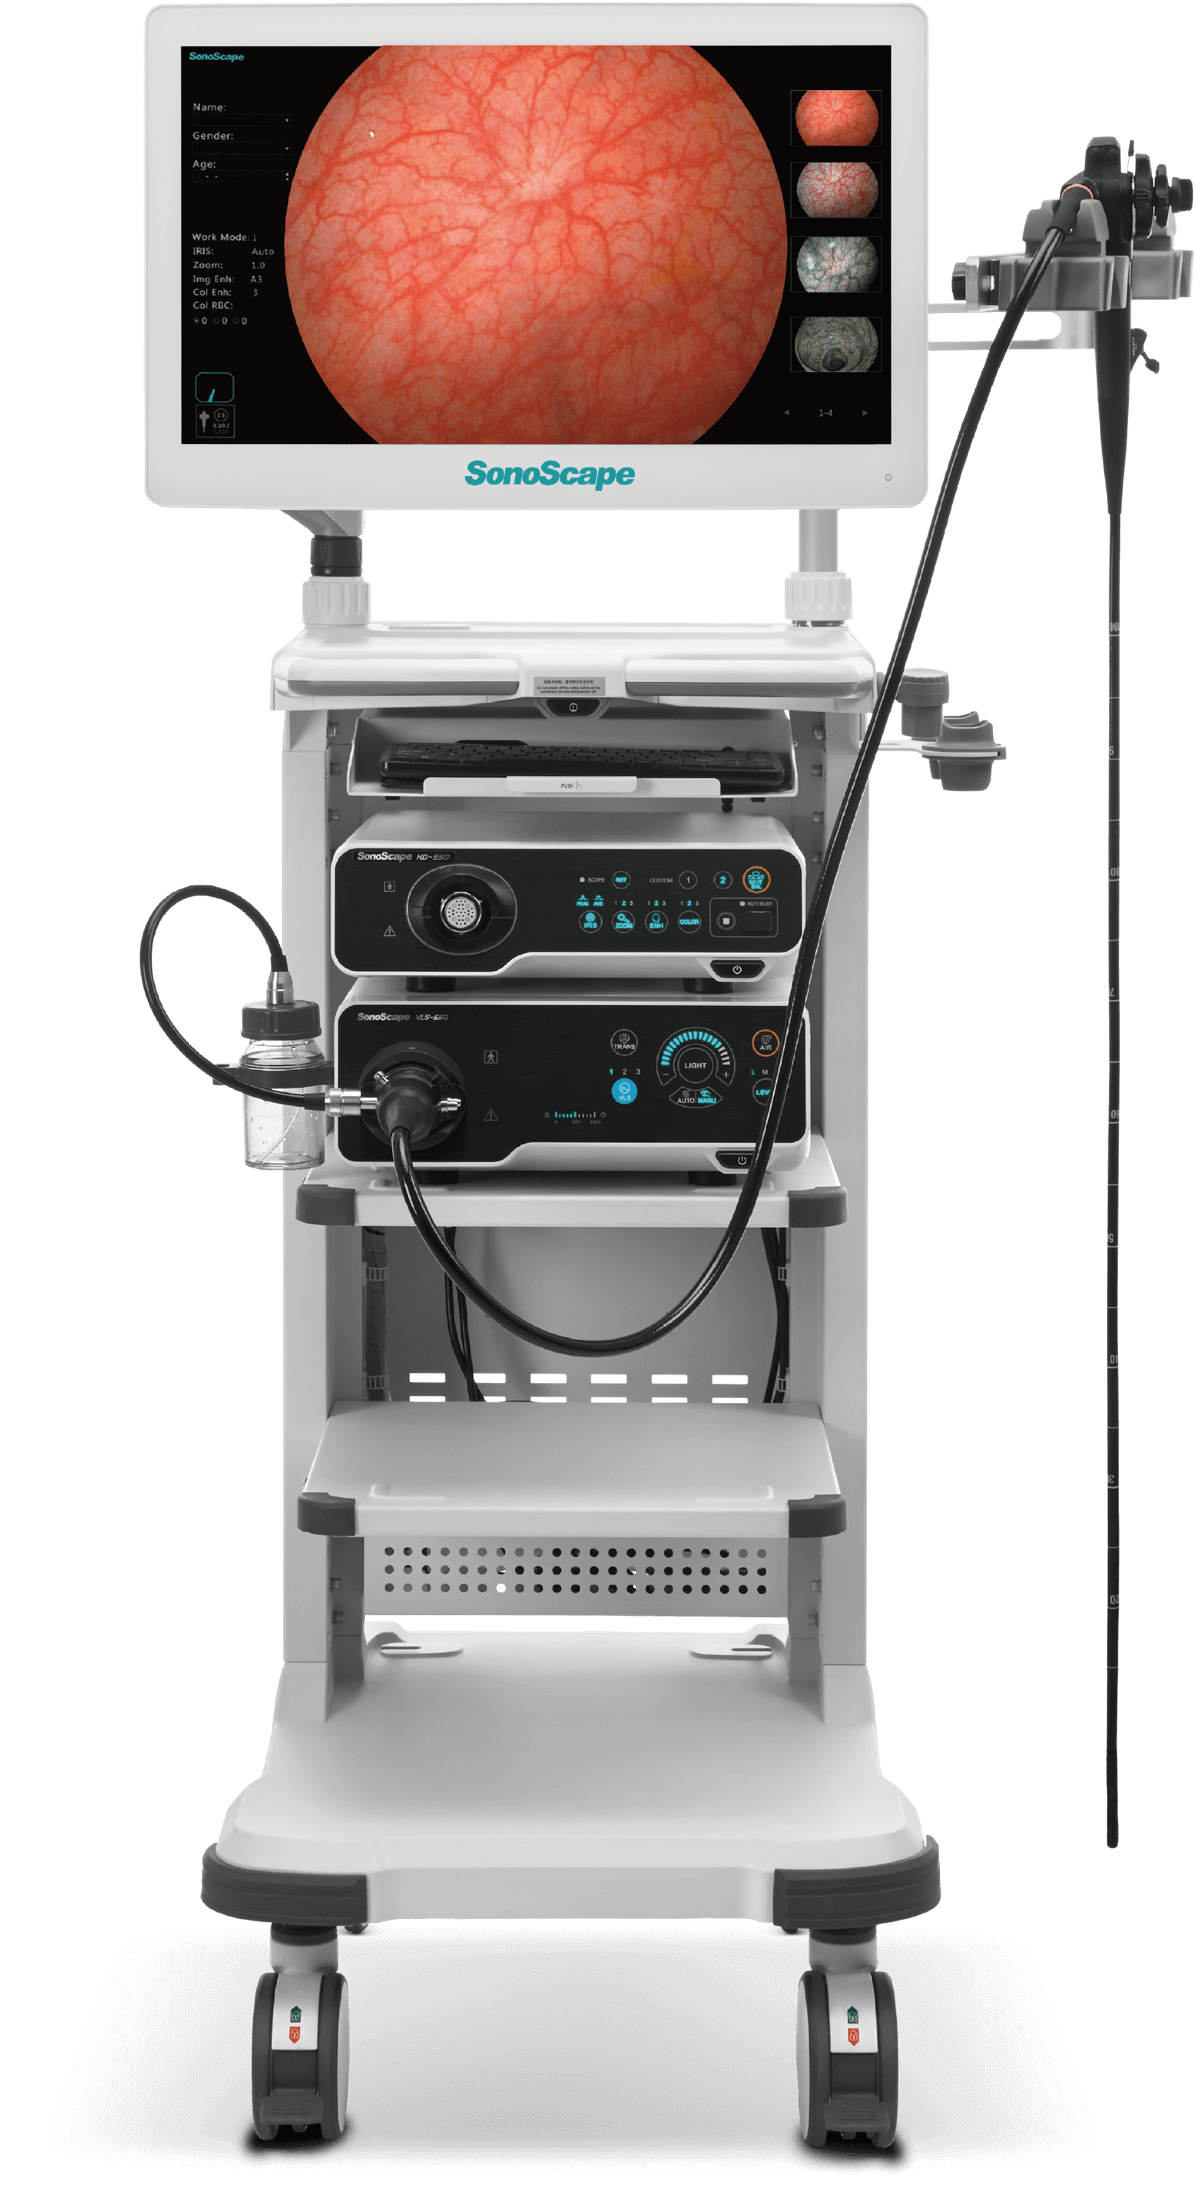

SV-M2K30

全高清内窥镜摄像系统

全高清内窥镜摄像系统

采用3片CMOS图像传感器,输出1920*1080P、60FPS全高清数字信号,提供稳定的腔镜视野,给予术者极佳的视觉体验,让手术更轻松,更精细!

是一种基于血红蛋白对不同波长光吸收系数不同的原理而设计的智能染色成像系统,兼有电子染色和光学染色功能,能够凸显粘膜血管结构,有助于病灶部位识别和诊断,为临床医生术中判断提供参考信息。

VIST光谱

光电复合染色成像

提供两种冷光源选择方案,氙灯更亮更接近自然光,呈现图像效果更真实、更有层次感。LED灯寿命长更经济环保,且提供多光谱输出,可提高微小病变的检出率。

氙灯

LED灯